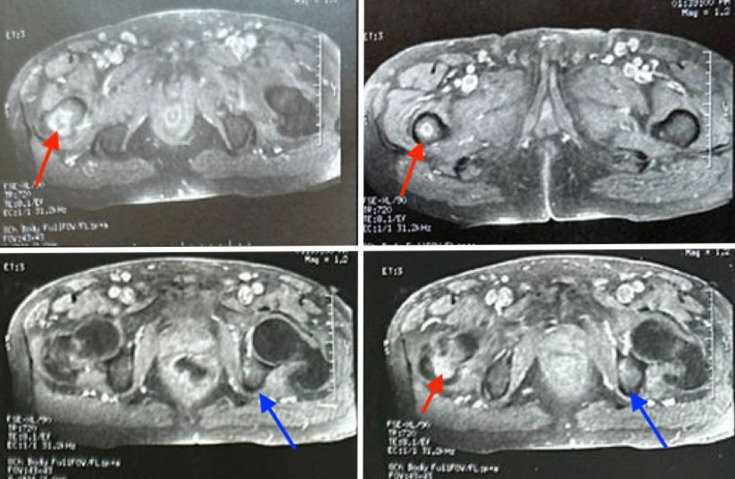

Tuberculosis (TB) remains one of the world's leading causes of morbidity and mortality. It occurs in both pulmonary and extra-pulmonary forms. Primary iliac bone TB remains a rare clinical entity, even in endemic areas. The diagnosis of the disease can be challenging due to its similarity to other bone diseases. We report a rare case of primary iliac bone TB in a 63-year-old patient who was on peritoneal dialysis and had a medical history of hypertension and type II diabetes, which was complicated by diabetic retinopathy and diabetic kidney disease. Magnetic resonance imaging revealed osteomyelitis in the iliac bone, while real-time polymerase chain reaction using the GeneXpert® system on a gluteal collection sample confirmed the diagnosis of TB. The integration of advanced molecular tools, such as GeneXpert®, represents significant progress, enabling rapid and accurate diagnosis of TB and facilitating early initiation of treatment.

Abstract Image